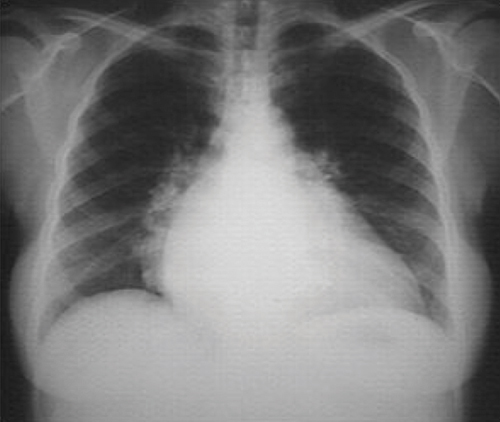

Seen in the chest x-ray, there are cardiomegaly and signs of pulmonary venous congestion with interstitial edema. Electrocardiagrams can also show disorders of ventricular repolarization, alterations in STEMI, left branch block, sinus tachycardia, disturbances of rhythm and other conditions of note.